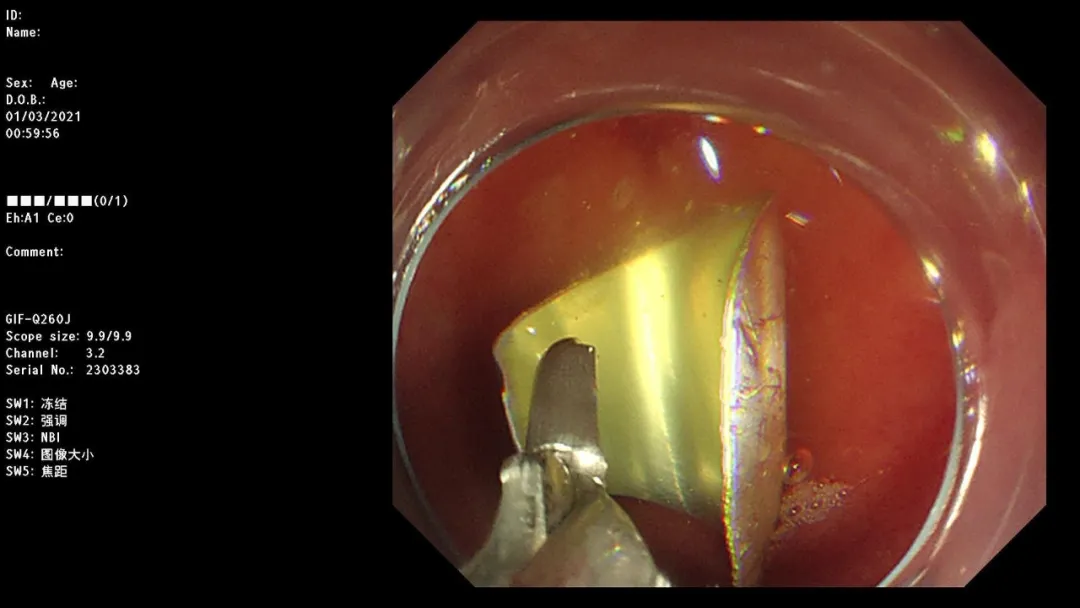

病例一:男,13岁,误食异物10小时,至儿科就诊。

South Africa red wine

急诊胃镜示:十二指肠球部可见异物,予异物钳取出,检查诊断:急诊异物取出术。